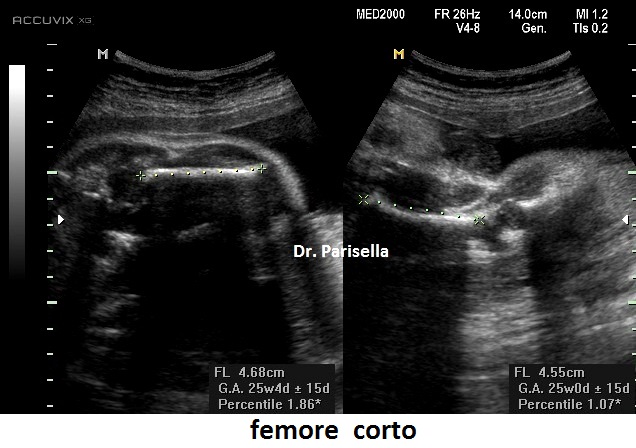

1. micromelia: è il segno più evidente, con gli arti inferiori al 5°percentile dopo la 20a-22a settimana; vi è anche brevità rizomelica che interessa principalmente i femori.

2.    femore corto con coscia che presenta un aumentato spessore del sottocute.

Un cenno a parte merita la distinzione tra forme eterozigoti ed omozigoti. Uno studio di Patè et al. ha riportato differenze tra le curve di crescita del femore nelle forme omozigoti ed eterozigoti.  I feti con acondroplasia omozigote presentavano un accorciamento del femore al disotto del 3° percentile già a 14 - 17 settimane, mentre i feti con acondroplasia eterozigote mostravano un accorciamento del femore al disotto del 3° percentile a 18 - 26 settimane.